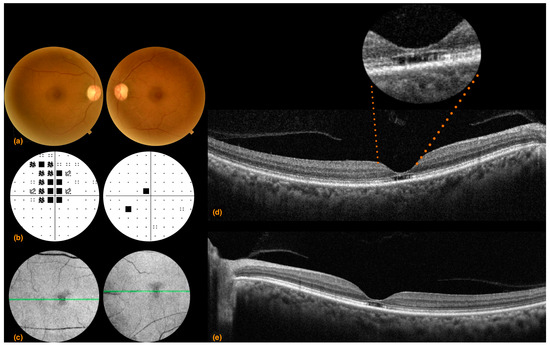

3.1. Case 1